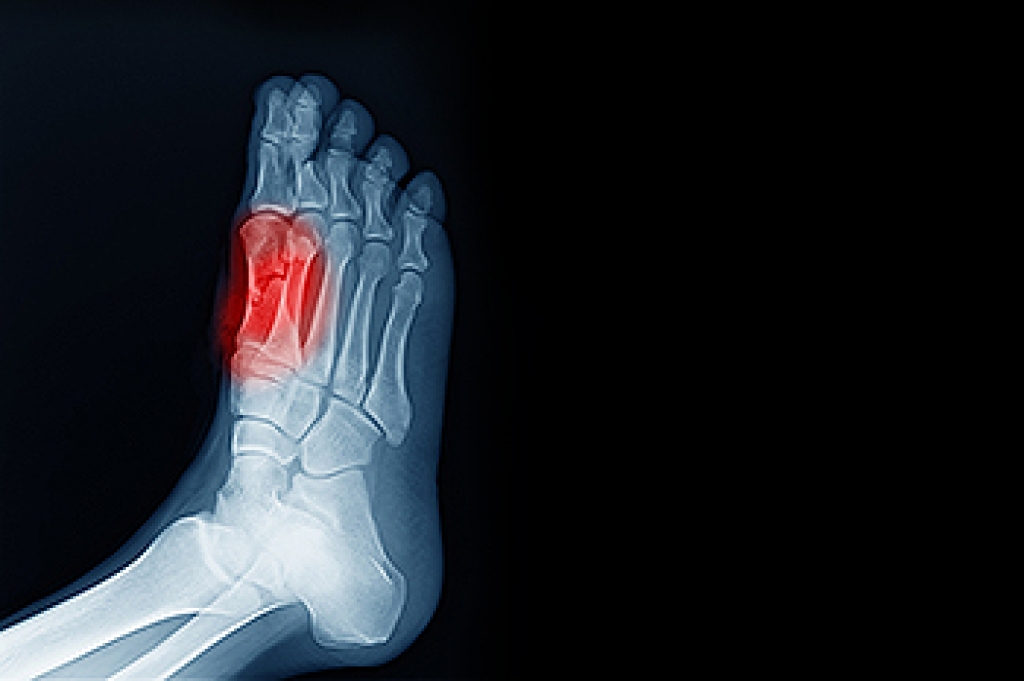

Achilles tendon injuries are diagnosed by a thorough physical evaluation, which can include an MRI. Treatment involves rest, physical therapy, and in some cases, surgery. However, various preventative measures can be taken to avoid these injuries, such as: